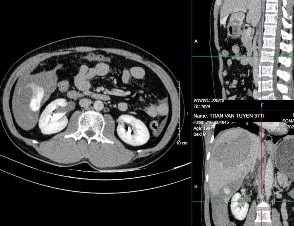

Hình 4.2: CTG độ III. Tụ máu dưới bao 7mm. Phân thùy sau có đường vỡ kèm tụ máu trong nhu mô gan kích thước 49 x 58mm, xung quanh có rối loạn tưới máu nhu mô.

Nguồn: BN Nguyễn Thị T, 60t HS: 2113618